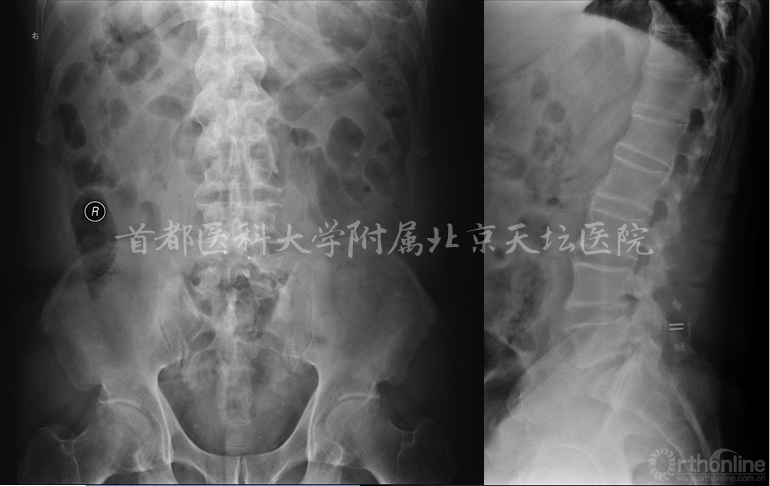

主诉:腰椎术后6年,腰痛1年,进行性加重伴双下肢麻木无力8个月

现病史:患者6年前出现腰痛伴右下肢放射痛,麻木及无力,于外院行棘突间内固定装置(Wallis)手术,术后症状部分缓解,未复查。1年前患者再次出现腰痛及下肢放射痛,8个月来呈进行性加重,现疼痛剧烈,不能久坐,不能站立及行走,平卧位不能缓解,服用止痛药物效果不佳。

既往史:脑梗死11年,右侧肢体力弱。肺间质纤维化10年。高血压病、糖尿病、高脂血症。

查体:腰部后正中长约5cm手术瘢痕,腰部软组织广泛压痛,腰部活动受限。双下肢小腿外侧、双足感觉减退,部分肌力4级,双侧肌张力正常。

双侧膝腱、跟腱反射未引出,双侧膑踝阵挛(-),双侧Hoffmann(+)、Babinsiki征(+)

评分:

VAS 腰部 8分 双下肢 6分

ODI(45分) 84.4%

BMI 35.2 骨密度 T值 -3.4 (Ward三角)

影像资料:

诊断:

• 腰椎管狭窄症(双侧神经根管狭窄)

• 棘突间植入物术后(Wallis)

• 棘突骨折

• 骨质疏松症